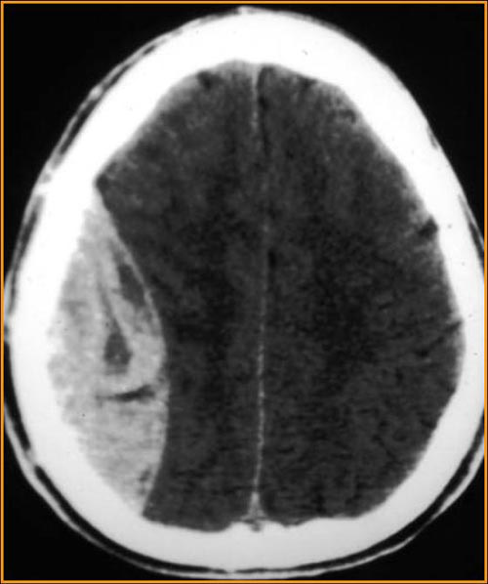

What is this? Where is the blood accumulating?

epidural hematoma

blood accumulates between the skull and dura mater

What vessel is most commonly torn in epidural hematomas?

middle meningeal artery

Can subdural hematoma blood cross skull suture line?

no